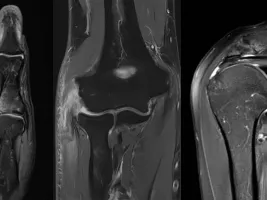

This cross-sectional imaging fellowship will highlight the pre-op and post-op imaging and clinical correlations of different joint derangements in the body including hip, shoulder, knee, ankle, wrist, and elbow among other smaller joints. Various procedures for osteochondral lesions, ligament, tendon, and pulley-plate reconstructions will be discussed with pre- and post-intervention normal and abnormal imaging appearances, particularly on MRI.

The modalities used during the course will be X-rays, CT, and MRI.